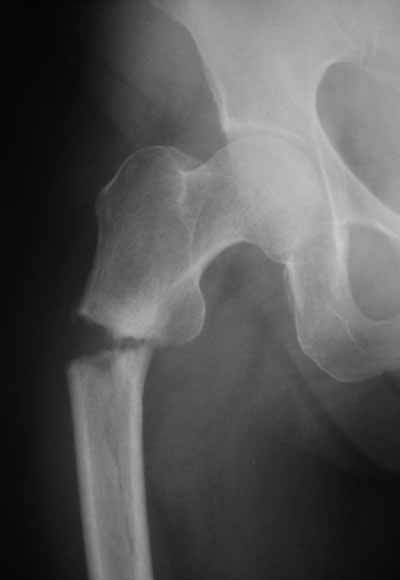

Александр упомянул, что выбранный шеечный винт коротковат, и именно поэтому я бы не советовал давать полную нагрузку на оперированную ногу (насколько это возможно у 72 летней больной)

-Субкапитальная зона шейки -слабое место и поэтому, если проведенный винт расположен именно в этой зоне, а не проведён дальше в головку, то есть опасность его миграции: при нагрузке создается опрокидывающий момент и винт разрушает верхний отдел шейки. При правильно выбранном размере винта нагрузку можно начинать сразу, критерий величины нагрузки - болевые ощущения.

Боковая проекция нужна всегда, иногда послеоперационные снимки преподносят неожиданные сюрпризы:-(( даже при использовании ЭОПа интраоперационно.

Надеюсь в вашем случае этого не случится, но лучше перестраховаться.